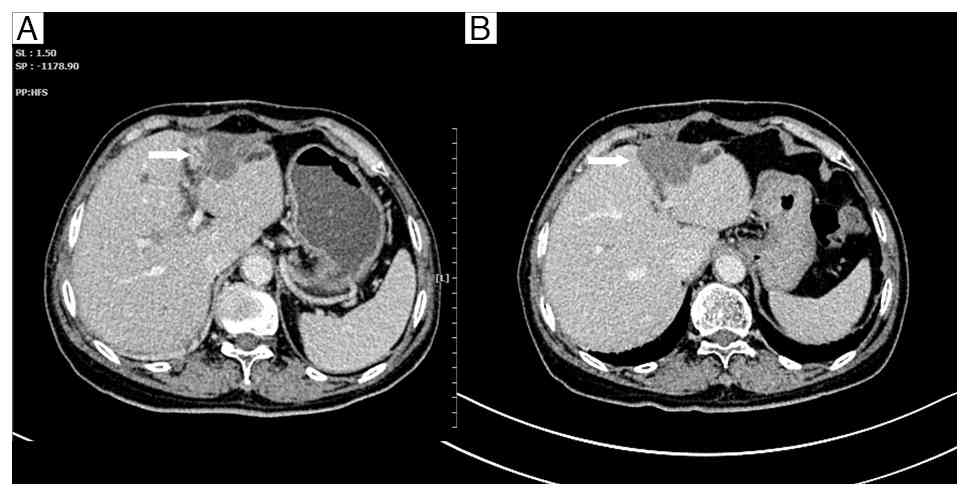

Enhanced computed tomography scans

following transarterial chemoembolization. (A) The lesion beneath

the liver capsule in the right lobe shows no significant reduction

in size compared with before, with mild enhancement (arrow). (B)

The lesion adjacent to the portal vein in the right lobe still

shows mild enhancement (arrow). (C) The lesion at the apex of the

right lobe of the liver shows no significant reduction in size

compared with before, with mild enhancement (arrow).

Figure 4.

Enhanced computed tomography scans following transarterial chemoembolization. (A) The lesion beneath the liver capsule in the right lobe shows no significant reduction in size compared with before, with mild enhancement (arrow). (B) The lesion adjacent to the portal vein in the right lobe still shows mild enhancement (arrow). (C) The lesion at the apex of the right lobe of the liver shows no significant reduction in size compared with before, with mild enhancement (arrow).